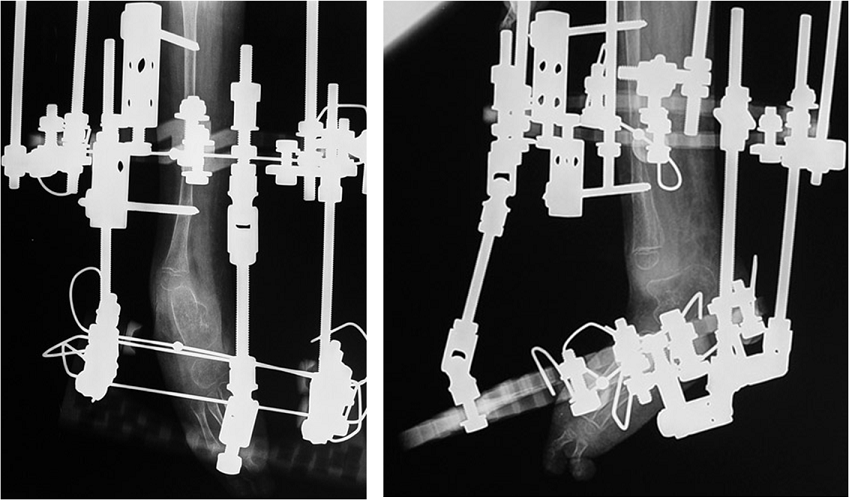

Congenital Pediatric Orthopedic DiseasesDec 30, 2021 | Case ExamplesBilateral GKD Case 1 Bilateral GKD Case 2 Bilateral GKD Case 3 Bilateral GKD Case 4 Congenital Clubfoot Fibuler Hemimeli Tibial Hemimeli PFFD